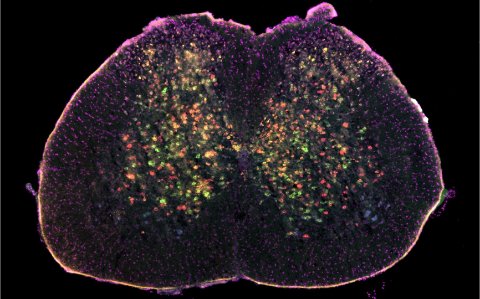

To make this discovery, the researchers developed an AI-based method to identify the cell types contributing to the disease – cells in the spinal cord tissue specifically. Dr Roser Montañana-Rosell, first author of the study, said these different cell types are “intermingled” within the spinal cord and are “often difficult to investigate simultaneously”.